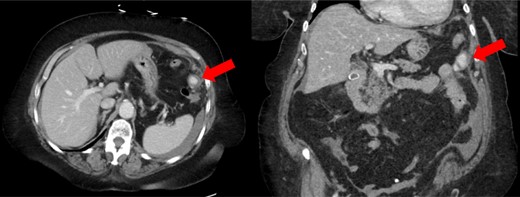

A 72-year-old female with a past medical history of chronic obstructive pulmonary disease, gastroesophageal reflux disease, hyperlipidemia, coronary artery disease and paroxysmal atrial fibrillation on warfarin (2.5 mg daily taken for several years) presented to a referring facility emergency department with worsening abdominal pain throughout the day. The patient had taken warfarin for several years without previous complications. Furthermore, she had no history of trauma or spontaneous bleeding. Her initial vital signs were unremarkable. Significant laboratory values included a hemoglobin of 13.0 and an international normalized ratio (INR) of 3.57, whereas all other labs were within normal limits. Cross-sectional imaging was obtained and the computed tomography (CT) scan revealed a left omental lesion measuring 2.2 cm with arterial and portal/venous enhancement concerning for a complex pseudoaneurysm (Fig. 1). Imaging also revealed a moderate volume (estimated 1000 cc) of hemoperitoneum. Given these findings, the patient was transferred to our facility for definitive care.

CT scan showing enhancing pseudoaneurysm (red arrow) with associated hemoperitoneum around the spleen, liver, and in left the paracolic gutter.